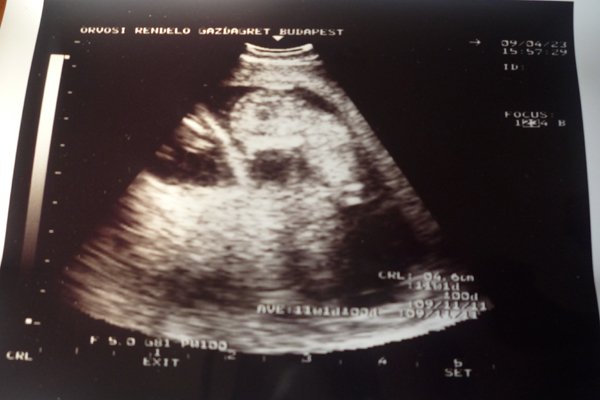

Dita: bocsi, de elfelejtettem leírni, hogy mekkorák. Tegnap voltak 4,6 cm-esek, mindketten!!! Egyénként a képeken lehet látni a méretüket is a CRL felirat mögött kivehető. :) És igen, őrület, hogy már ilyenkor megvan mindenük!!!! :D :D